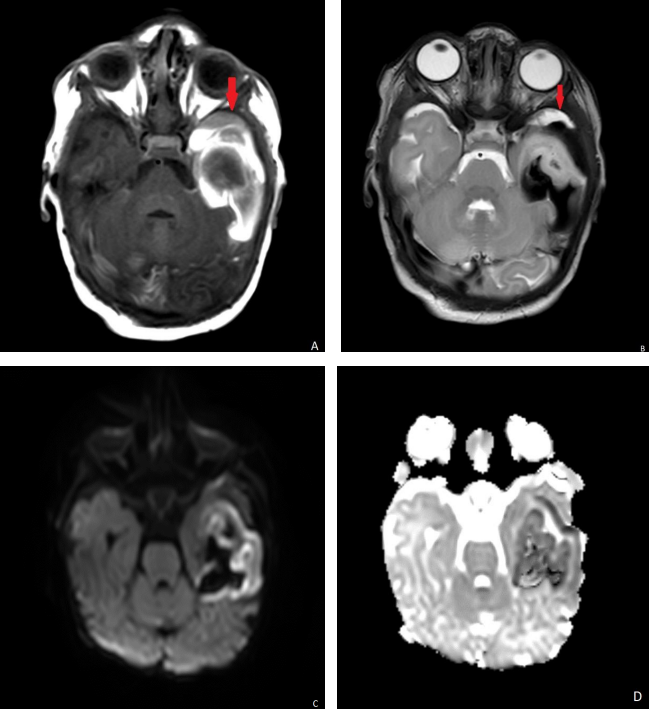

Ultrasound head showed left temporal lobe increased echogenicity with loss of normal gray-white matter differentiation with no flow on Doppler interrogation most likely represent hemorrhage. (Fig. 1). MRI scan was done on day 6 showed extra axial hemorrhage with high signal intensity on T1-weighted images and low signal intensity on T2-weighted images in the left temporal lobe opposing the underlying sulci and separate from the adjacent CSF (Fig. 2A and B). It showed mass effect on the adjacent cortex with cortical high signal intensity on T1 and T2-weighted images with evidence of diffusion restriction (Fig2 C, D). The final diagnosis was subpial hemorrhage with adjacent cortical hemorrhagic infarction.

Imaging criteria described as extra axial hemorrhage along the margin of the cerebral parenchyma extending into the cerebral sulci under the pia matter. The adjacent cortes show venous congestion or infarction in most of the cases.

The appearance of the hemorrhage described by Assis Z (1) as Yin-yang symbol with hypointense subpial hemorrhage and the underlying hyperintense cerebral cortex on T2-weighed image. The most common location of the hemorrhage is temporal lobes, followed by the frontal, parietal and occipital lobes. (5)

Figure 1

Figure 2